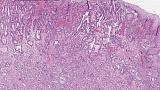

Иллюстрация №3: Рис. 3. Аденокарцинома пищевода. Окраска HE, увеличение х 100

При поступлении в нашу клинику, по результатам пересмотра предоставленного гистологического материала был подтверждён диагноз аденокарциномы (рис. 3). При повторной эзофагогастродуоденоскопии в области кардиоэзофагеального перехода было обнаружено эпителиальное образование Is типа, размерами до 15 х 20 мм, высотой до 8 мм. При осмотре в узком спектре света (NBI) с использованием функции двойного фокуса имелась отчётливая демаркационная линия между новообразованием и окружающей его слизистой оболочкой, а в его центральной части микрососудистый рисунок имел нерегулярный характер, ямочный рисунок поверхности эпителия был разрушен, что согласно VS-классификации K.Yao характерно для неопластических изменений (рис. 4 a, b). Просвет «малого» вновь сформированного желудка расправлялся не полностью, складки были утолщены, слизистая оболочка отечная, гиперемирована. Гастроэнтероанастомоз широкий, эластичный, слизистая оболочка его отечная, незначительно гиперемирована, без язв и эрозий. Слизистая оболочка анастомозированной тонкой кишки без особенностей.

Морфологическое и иммуногистохимическое заключение: тубулярная аденокарцинома пищеводно‑желудочного перехода, grade I. Опухоль прорастает в верхнюю треть подслизистого слоя (sm1), pT1b. Васкулярной инвазии не выявлено (Ly «-», V «-»), в краях препарата признаков опухолевого роста не выявлено (LM «-», VM «-»), R0 (рис. 9).